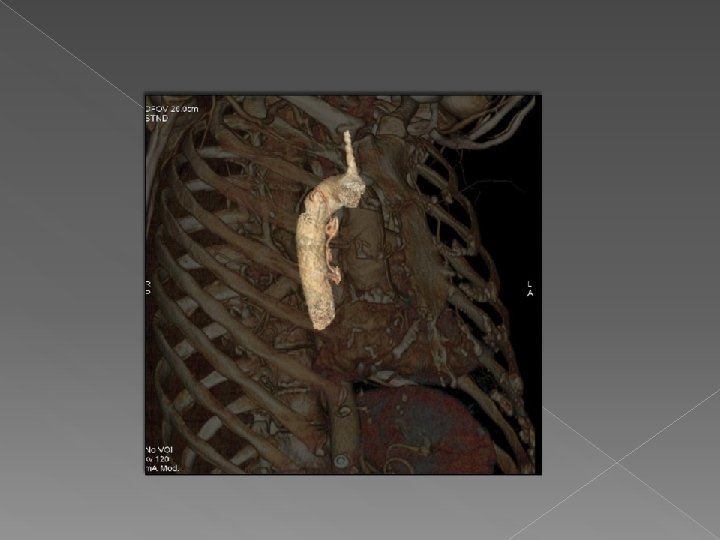

Valor de VR : se visualiza la arteria aferente que se origina en

Valor de VR : se visualiza la arteria aferente que se origina en la aorta y se dirige a la masa con un drenaje venoso a la vena pulmonar inferior derecha. Hallazgos sugestivos de secuestro pulmonar intralobar.

Drenaje venoso Secuestro pulmonar